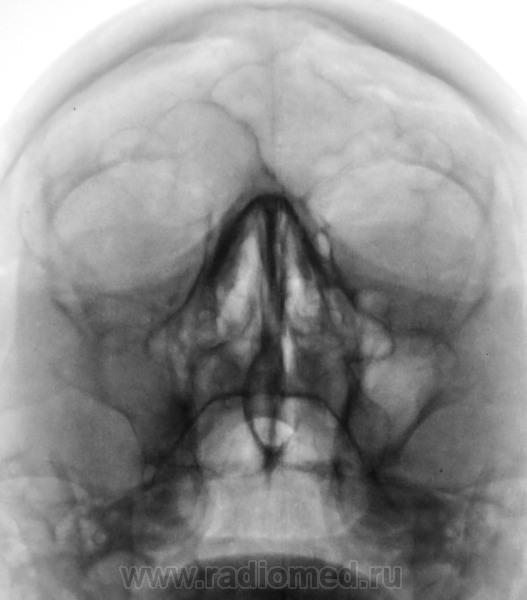

Тотальное затемнение левой гайморовой пазухи и субтотальное слева?

Гайморит с 2 сторон.

Слева тоже гайморит?

А линейку можно? Может киста. Но факт что затемнение есть.

Затемнение есть, не спорю. Но вот наружный контур "затемнения" уж сильно, и ровный, и четкий.

Утолщение слизистой слева, т. е. отек.

На "кисту" не танцует"

А в динамике м.б. вполне, но пока (мне кажется ) просто отек.

Слева в гайморовой пазухе беда. Плюс на левую орбиту из пазухи выходит сия беда. Пунктировать надо челюстно-лицевому хирургу (или кто вместо него) это место и в микроскоп смотреть гистологу (или кто вместо него). Думаю я, что это опухоль.